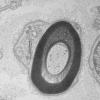

PERIPHERAL NEUROPATHY